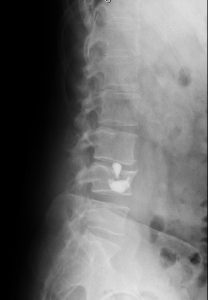

Se realizó cifoplastia uniportal derecha con sedación, con mejoría significativa de los síntomas.

Obsérvese migración del cemento al espacio intersomático.